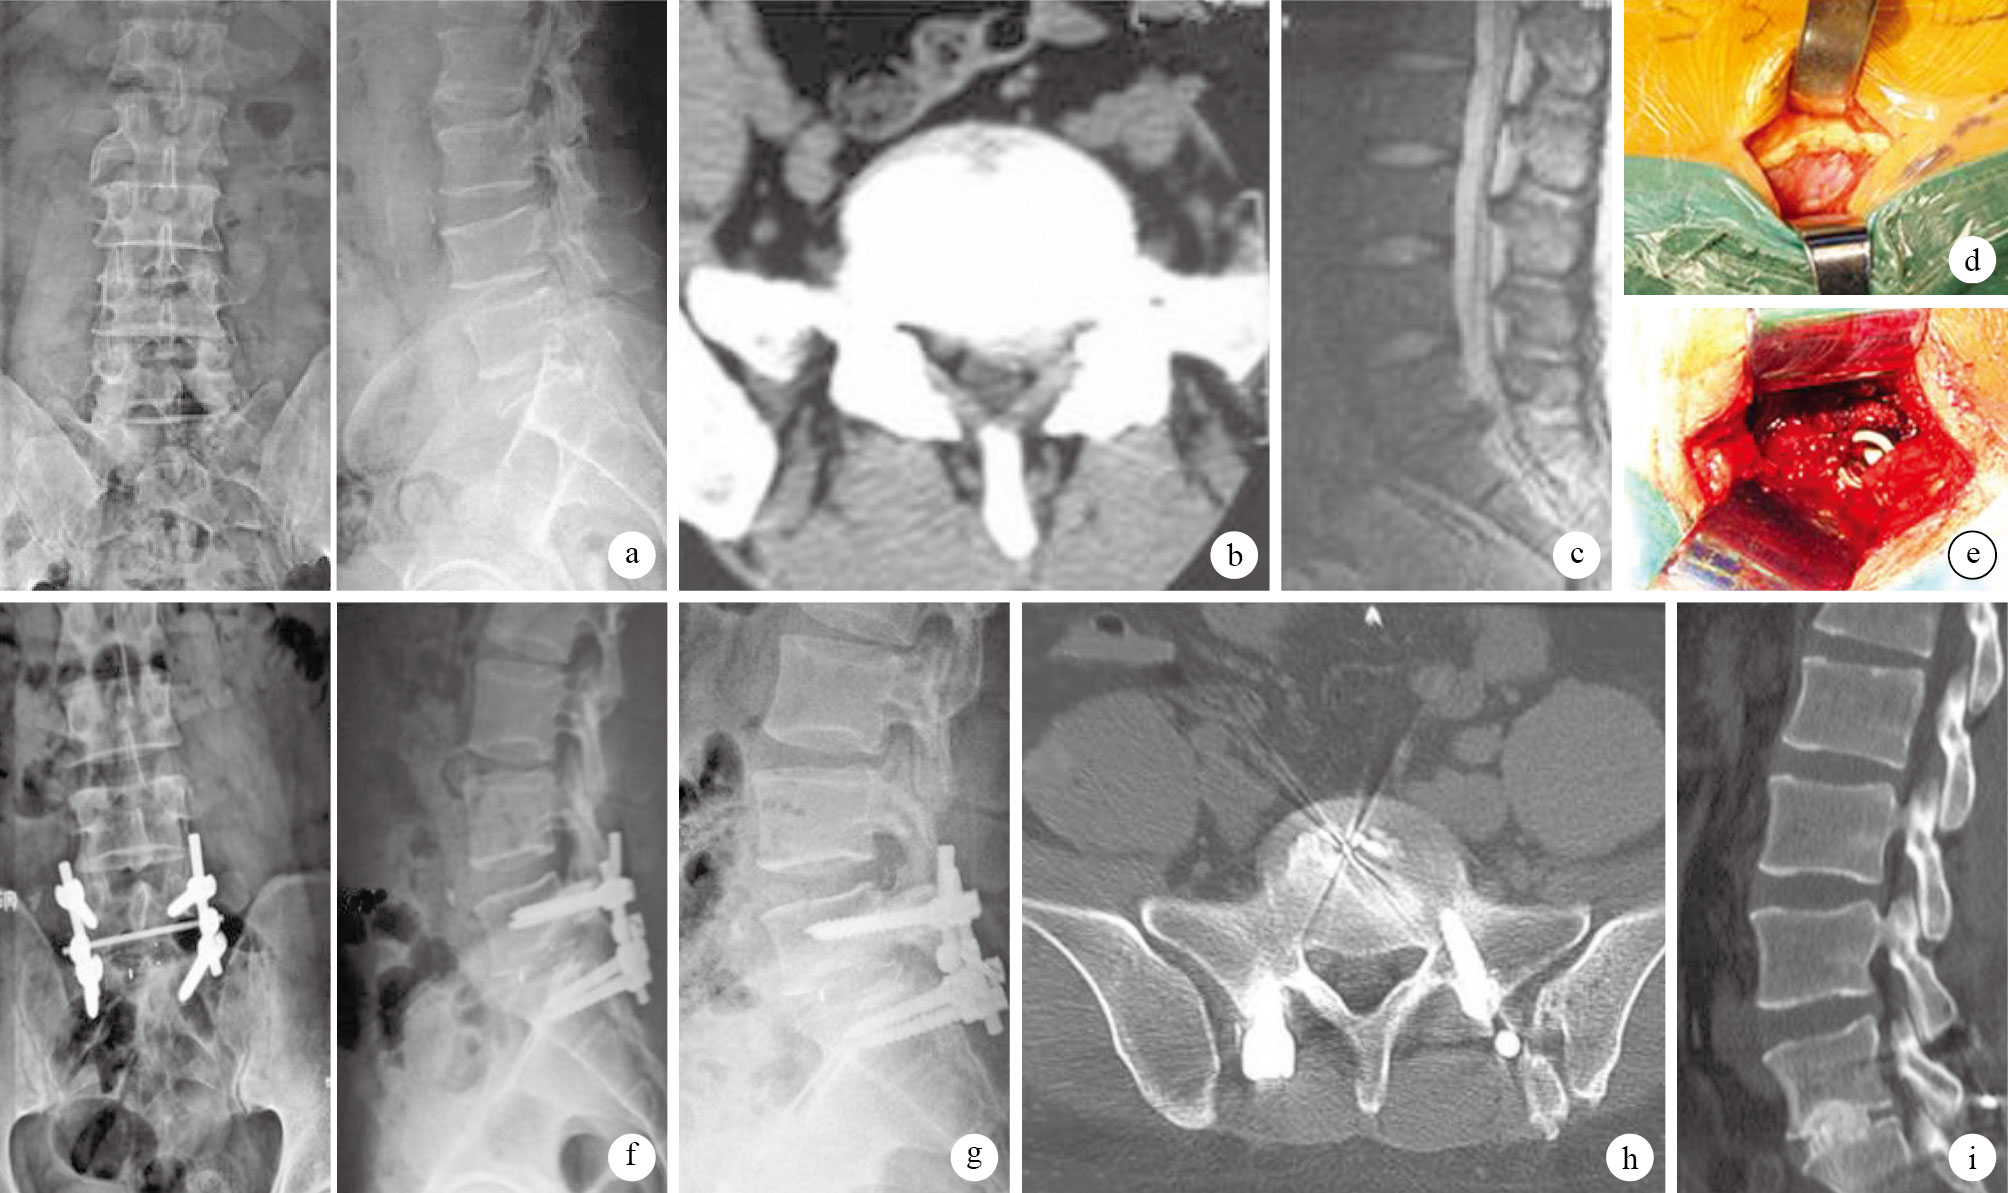

術后1年根據Suk標準[5],開放組獲椎間堅強融合18例、可能融合4例、不融合4例,椎間融合率為84.61%;微創組堅強融合21例、可能融合3例、不融合4例,椎間融合率為85.71%;兩組椎間融合率比較,差異無統計學意義(χ2=0.072,P=0.821)。見圖 1。